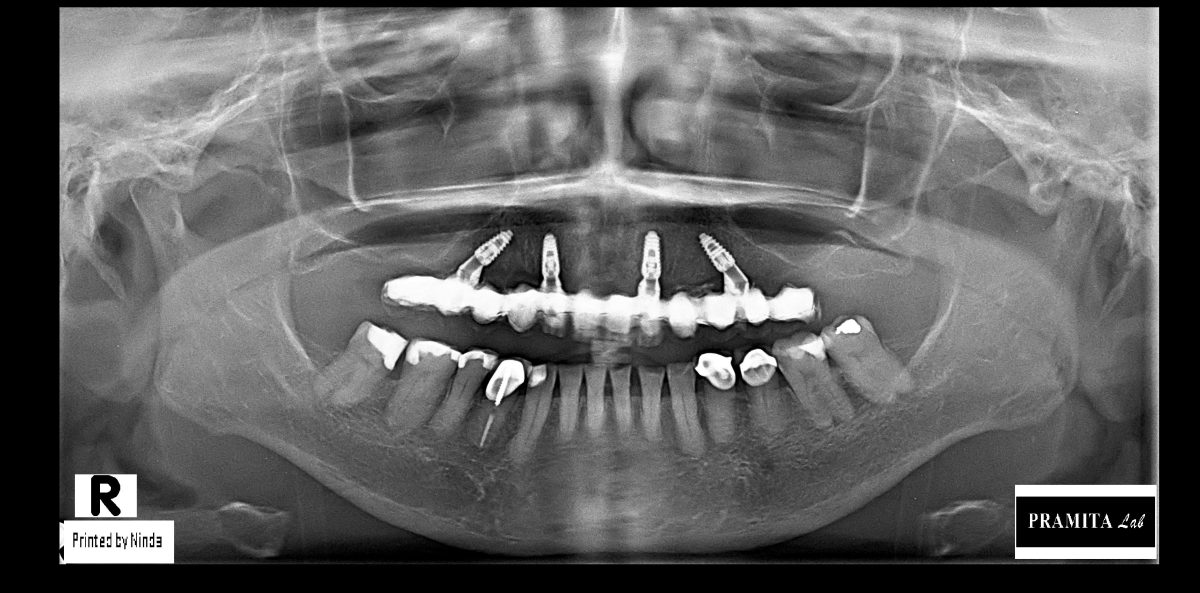

All-on-X dental implants are a full-arch restoration solution designed for patients with multiple missing, damaged, or failing teeth. The treatment uses four, five, or six dental implants to support a fixed full-arch prosthesis, restoring both function and aesthetics.

The number of implants required depends on bone condition, bite forces, and overall treatment planning.

A healing period of approximately 4–6 months allows osseointegration between the implants and jawbone.

The timeline depends on your case and bone condition.

Before your trip, our dentists can review your X-rays or scans and provide a personalized treatment timeline.